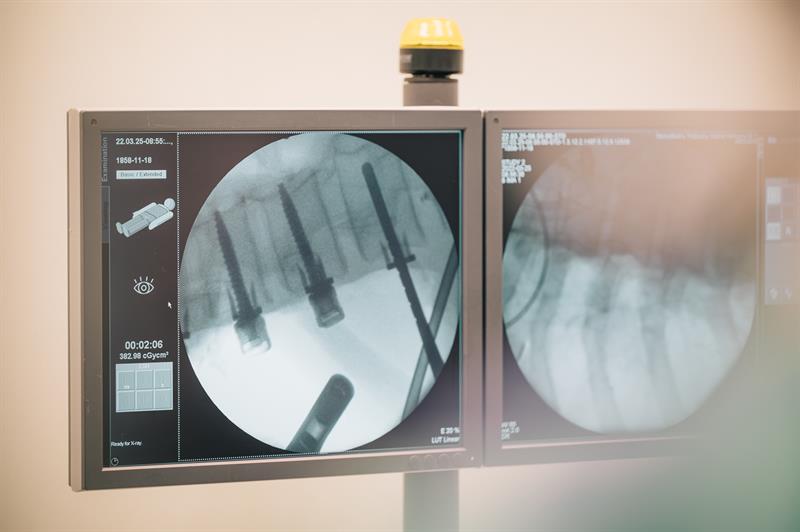

Operację wykonali ortopedzi: dr Sławomir Zacha, dr Aleksander Szwed, dr Bartosz Kruk; anestezjolodzy: doc. Jowita Biernawska, dr Jakub Miegoń; neurolog dr Monika Deptuła-Jarosz; pielęgniarka operacyjna Zdzisława Stankiewicz; pielęgniarka anestezjologiczna Justyna Krawczyk. Fot. SPSK-1 PUM w Szczecinie

W Europie takie zabiegi wykonywane są w nielicznych ośrodkach klinicznych. Po raz pierwszy, kilka dni temu, w naszym regionie zrobili to specjaliści z Kliniki Ortopedii Dziecięcej i Onkologii Narządu Ruchu SPSK 1 PUM w Szczecinie. To operacja skoliozy idiopatycznej u dziecka bez usztywnienia kręgosłupa. Pozwala zachować pełną ruchomość kręgosłupa i nie ograniczać jego wzrostu. Sama operacja jest niezbędna, żeby powstrzymać deformację, zagrażającą prawidłowemu funkcjonowaniu układu oddechowego i krążenia.

Lekarze z Kliniki Ortopedii Dziecięcej i Onkologii Narządu Ruchu Samodzielnego Publicznego Szpitala Klinicznego nr 1 Pomorskiego Uniwersytetu Medycznego w Szczecinie przeprowadzili, 25 marca tego roku, po raz pierwszy w regionie, operację korekcji skoliozy idiopatycznej u dziecka, nowatorską techniką bez usztywniania kręgosłupa, tzw. VBT (ang. Vertebral Body Tethering). W Europie takie zabiegi wykonywane są tylko przez nieliczne ośrodki kliniczne. Głównym celem jest powstrzymanie deformacji, która zagraża prawidłowemu funkcjonowaniu układu oddechowego i krążenia.